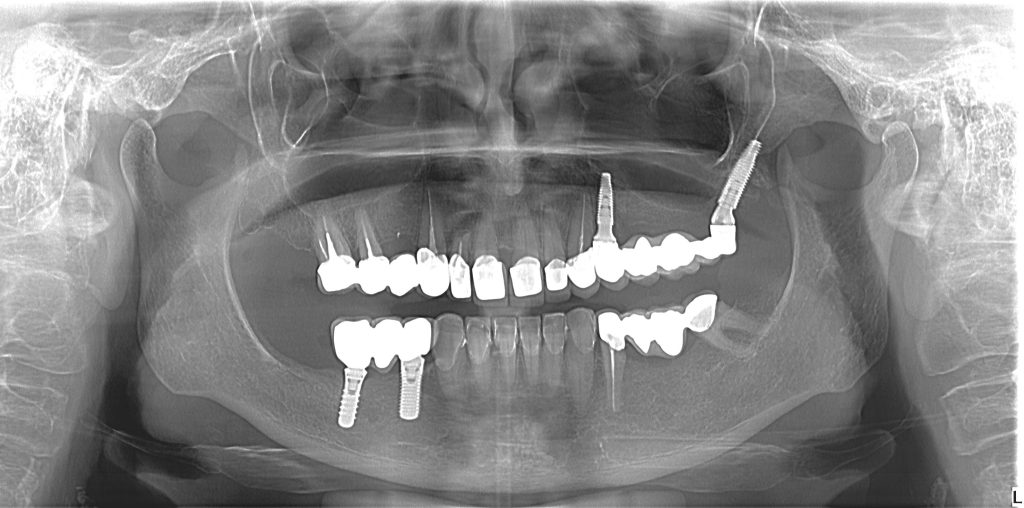

Low sinus floor indicates the need for pterygoid implant in a posterior dental bridge

Ultimately, within the Graft Free Implantology classification, this approach provides the essential framework for Level 2 (dental bridges) and Level 3 (full-arch) restorations when other options are exhausted. Despite their tremendous utility, pterygoid implants should always be indicated with critical caution. Not only do they demand profound anatomical knowledge and are notoriously difficult to position surgically, but meticulous care must also be dedicated to the prosthetic superstructure. Adequate restorative vertical space must be thoroughly evaluated prior to placement to ensure sufficient room for the final restoration. Furthermore, their extreme emergence angle can present a restorative challenge, frequently necessitating the use of severely angled abutments—sometimes up to 45 degrees. Consequently, comprehensive, top-down planning of all these surgical and prosthetic variables is mandatory before proceeding with their use.